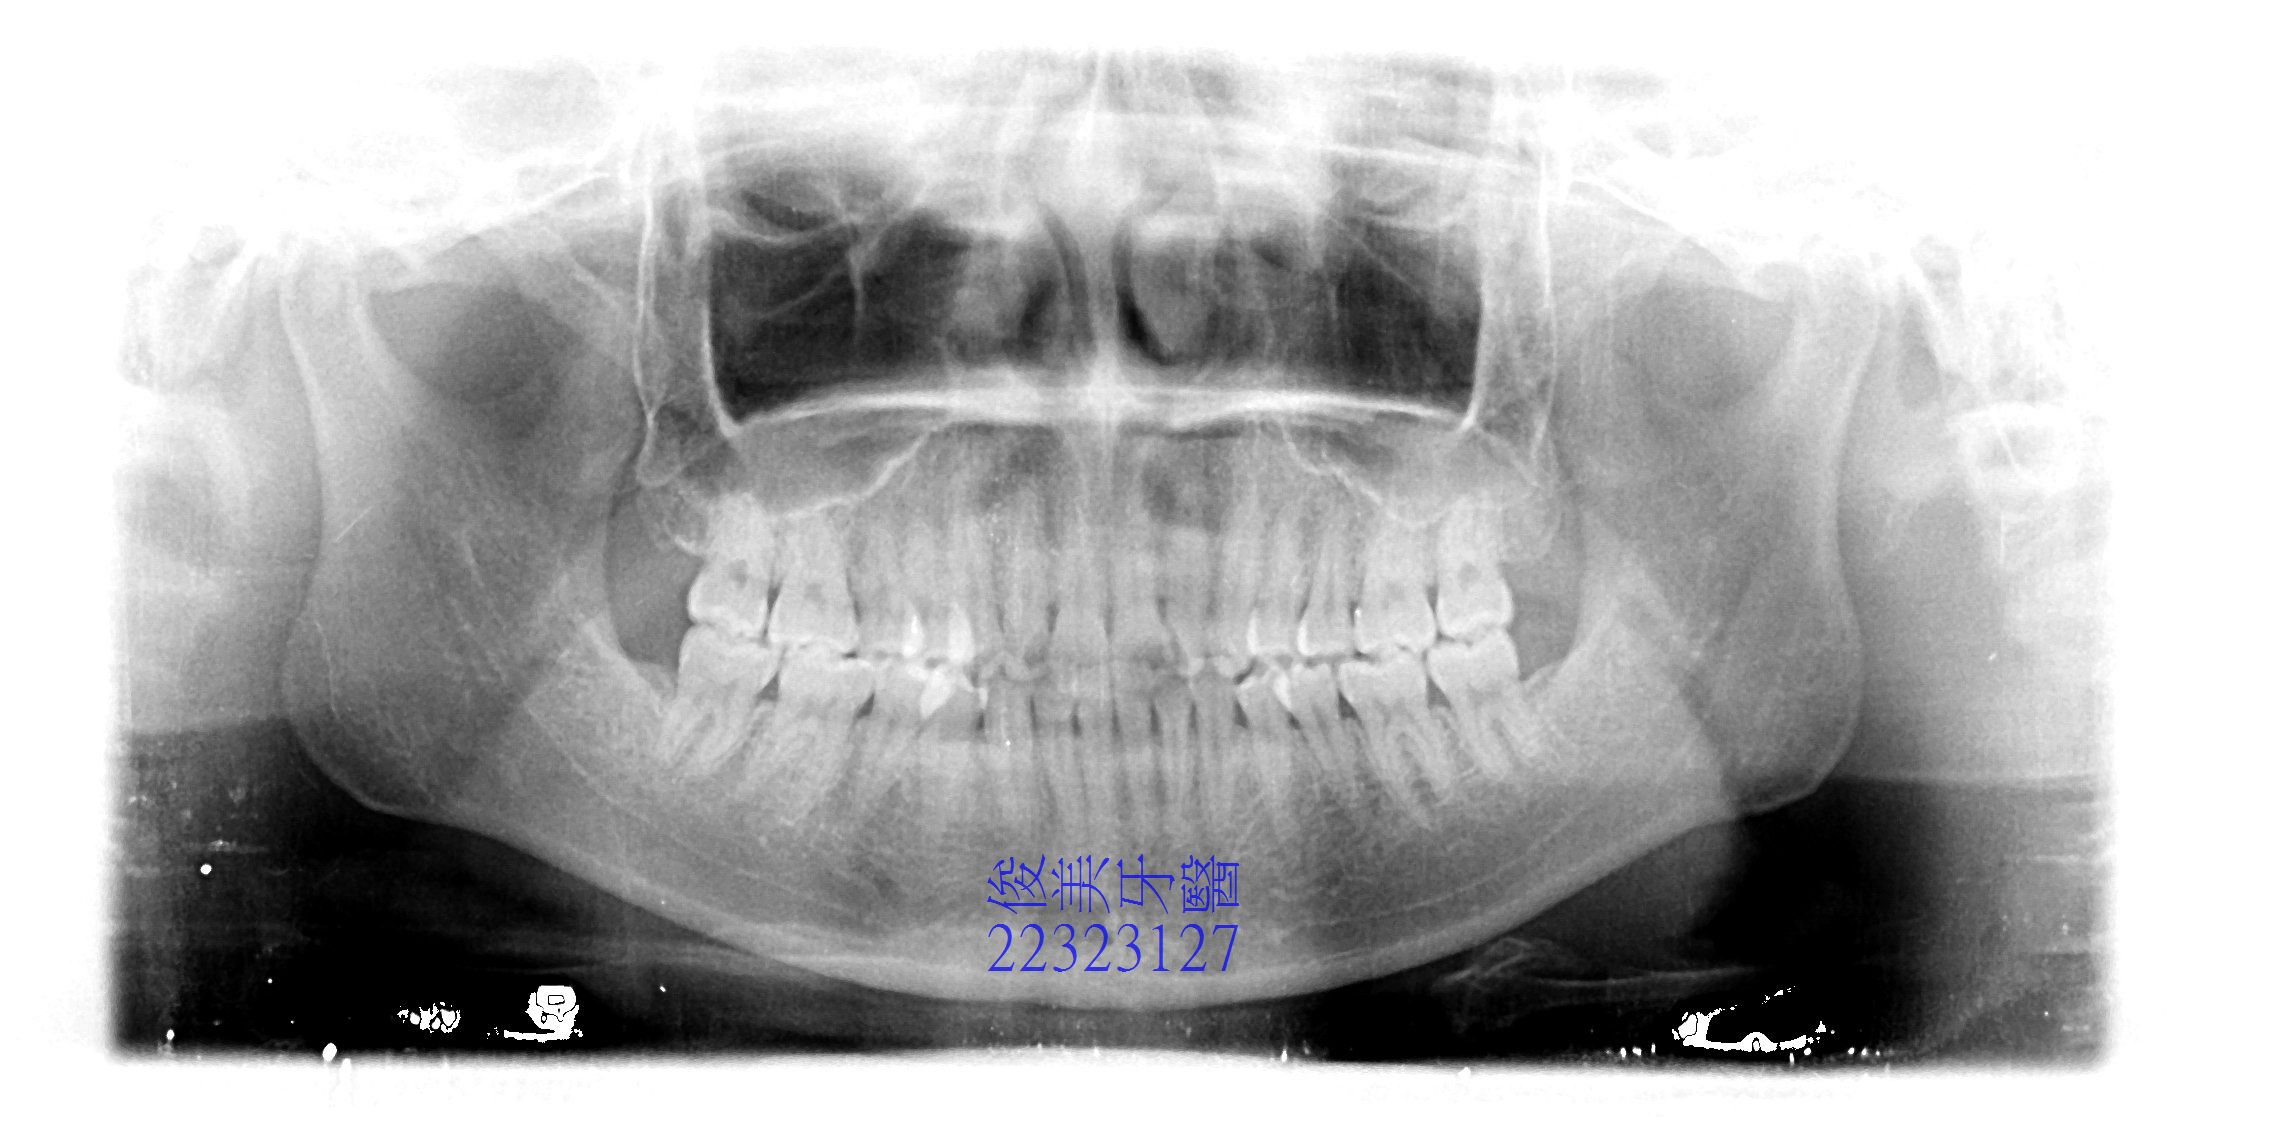

![]() 患者於門診中表示,牙齒很擁擠,想要改善;經醫師門診後,建議患者進行矯正治療即可改善。 ![]() 牙齒重疊... ![]() 有深咬現象... ![]() 上顎狀況... ![]() 下顎狀況... ![]() 左側咬合,牙齒往舌側傾斜...... . ![]() 右側咬合,牙齒往舌側傾斜...... ![]() 治療中....擁擠和深咬已改善.... ![]() 牙齒往後移.....將牙齒齒軸回正一點。 ![]() 治療結束,拆除矯正器了............. ![]() 患者好開心......牙齒整齊後,笑容更可愛了。 ![]() 也沒有暴牙的狀況。 ![]() 上顎牙弓狀況。 ![]() 下顎牙弓狀況。 ![]() 右側咬合狀況。 ![]() 左側咬合狀況。 ![]() 已拆除超過5年,依舊配戴維持器,保持最佳狀態。 |